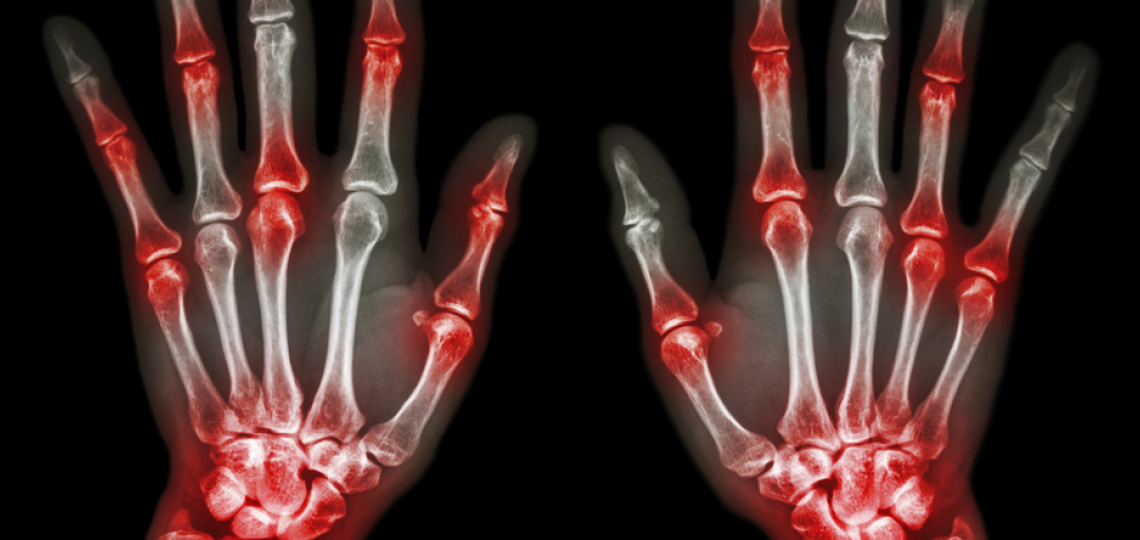

Conditions Treated

Rheumatology encompasses a variety of complex and multi-system conditions that are autoimmune or inflammatory in nature including:

- Inflammatory arthritis

- Rheumatoid Arthritis